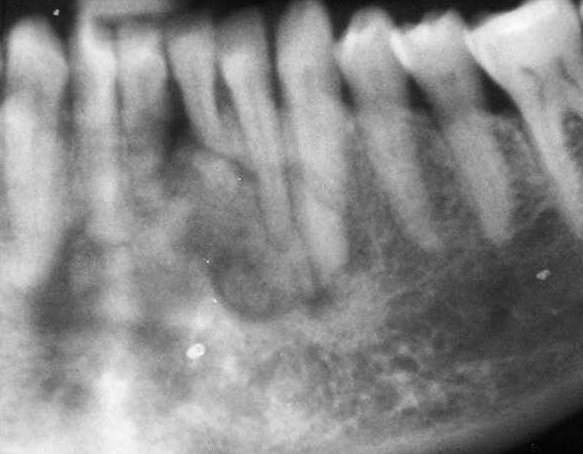

- Most common location: premolar / molar region of the mandible.

- Usually it is attached to the root of the affected tooth. Tooth displacement and root resorption are common findings.

- Three stages of development: radiolucent – mixed – radiopaque.

- When the lesion is radiopaque, it is usually surrounded by a thin radiolucent halo.